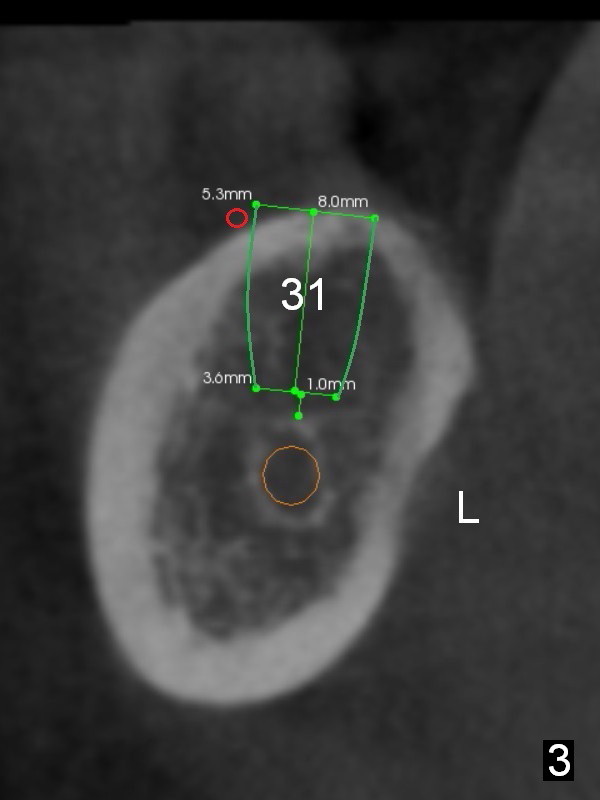

Fig.2 (sagitttal section) shows that the bone height at the site of #31 is shorter than that of #30. There is a 1 mm separation from the Inferior Alveolar Nerve (brown) if a 8 mm implant is placed at #31 (Fig.2,3 (coronal section)), whereas 3 mm separation for a 6 mm implant (Fig.4). Since the tooth #2 is supraerupted, the shorter implant at #31 is more appropriate. It is placed a little deeper (Fig.4' arrow) so that the abutment or the opposing tooth does not need to be trimmed too much. In addition, choose a widest abutment (purple, e.g., 7.8 mm) with the shortest cuff (pink, 1 mm). A splinted immediate provisional will be fabricated to prevent the gingiva from growing into the abutment margin. At restorative phase, a smaller abutment will be used (e.g., 5.8 mm) so that the gingiva is clear from the margin. It will be easy for impression. Then the provisional will be relined to keep the gingiva from growing into the space just created by changing abutments. Bone graft will be needed buccal to the implant at #31 (Fig.3,4 red circle; L: lingual).